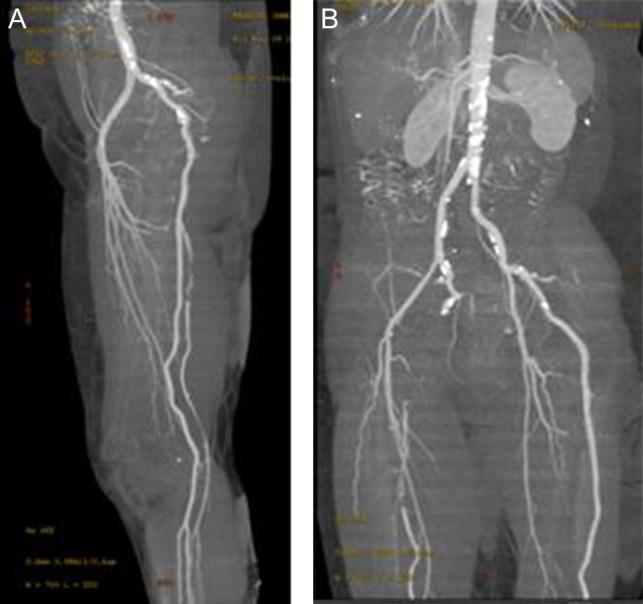

双侧持续性坐骨动脉并单侧急性下肢缺血。

Bilateral persistent sciatic arteries complicated by unilateral acute lower limb ischaemia.

We present a case of a middle-aged Caucasian woman who developed acuteon top of chronic limb ischaemia secondary to thrombotic occlusion of a persistent sciatic artery (PSA). Timely investigation and treatment were instituted resulting in a favourable outcome. PSA is an uncommon congenital, developmental, arterial anomaly which can cause serious lower limb complications such as acute or critical limb ischaemia and amputation. As this condition is rarely encountered in regular clinical practice, and has a limb-threatening potential, it is important to be aware of its cause, presentation and management. We describe the embryologic aetiology of PSA and discuss different investigation modalities and treatment options.

我们报告了一例中年白种女性病例,该患者在持续性坐骨动脉(PSA)血栓形成导致的慢性肢体缺血基础上发生急性病变。及时进行了检查和治疗,结果良好。PSA是一种罕见的先天性、发育性动脉异常,可导致严重的下肢并发症,如急性或严重肢体缺血及截肢。由于这种情况在常规临床实践中很少遇到,且具有肢体威胁性,因此了解其病因、表现和治疗方法很重要。我们描述了PSA的胚胎学病因,并讨论了不同的检查方式和治疗选择。